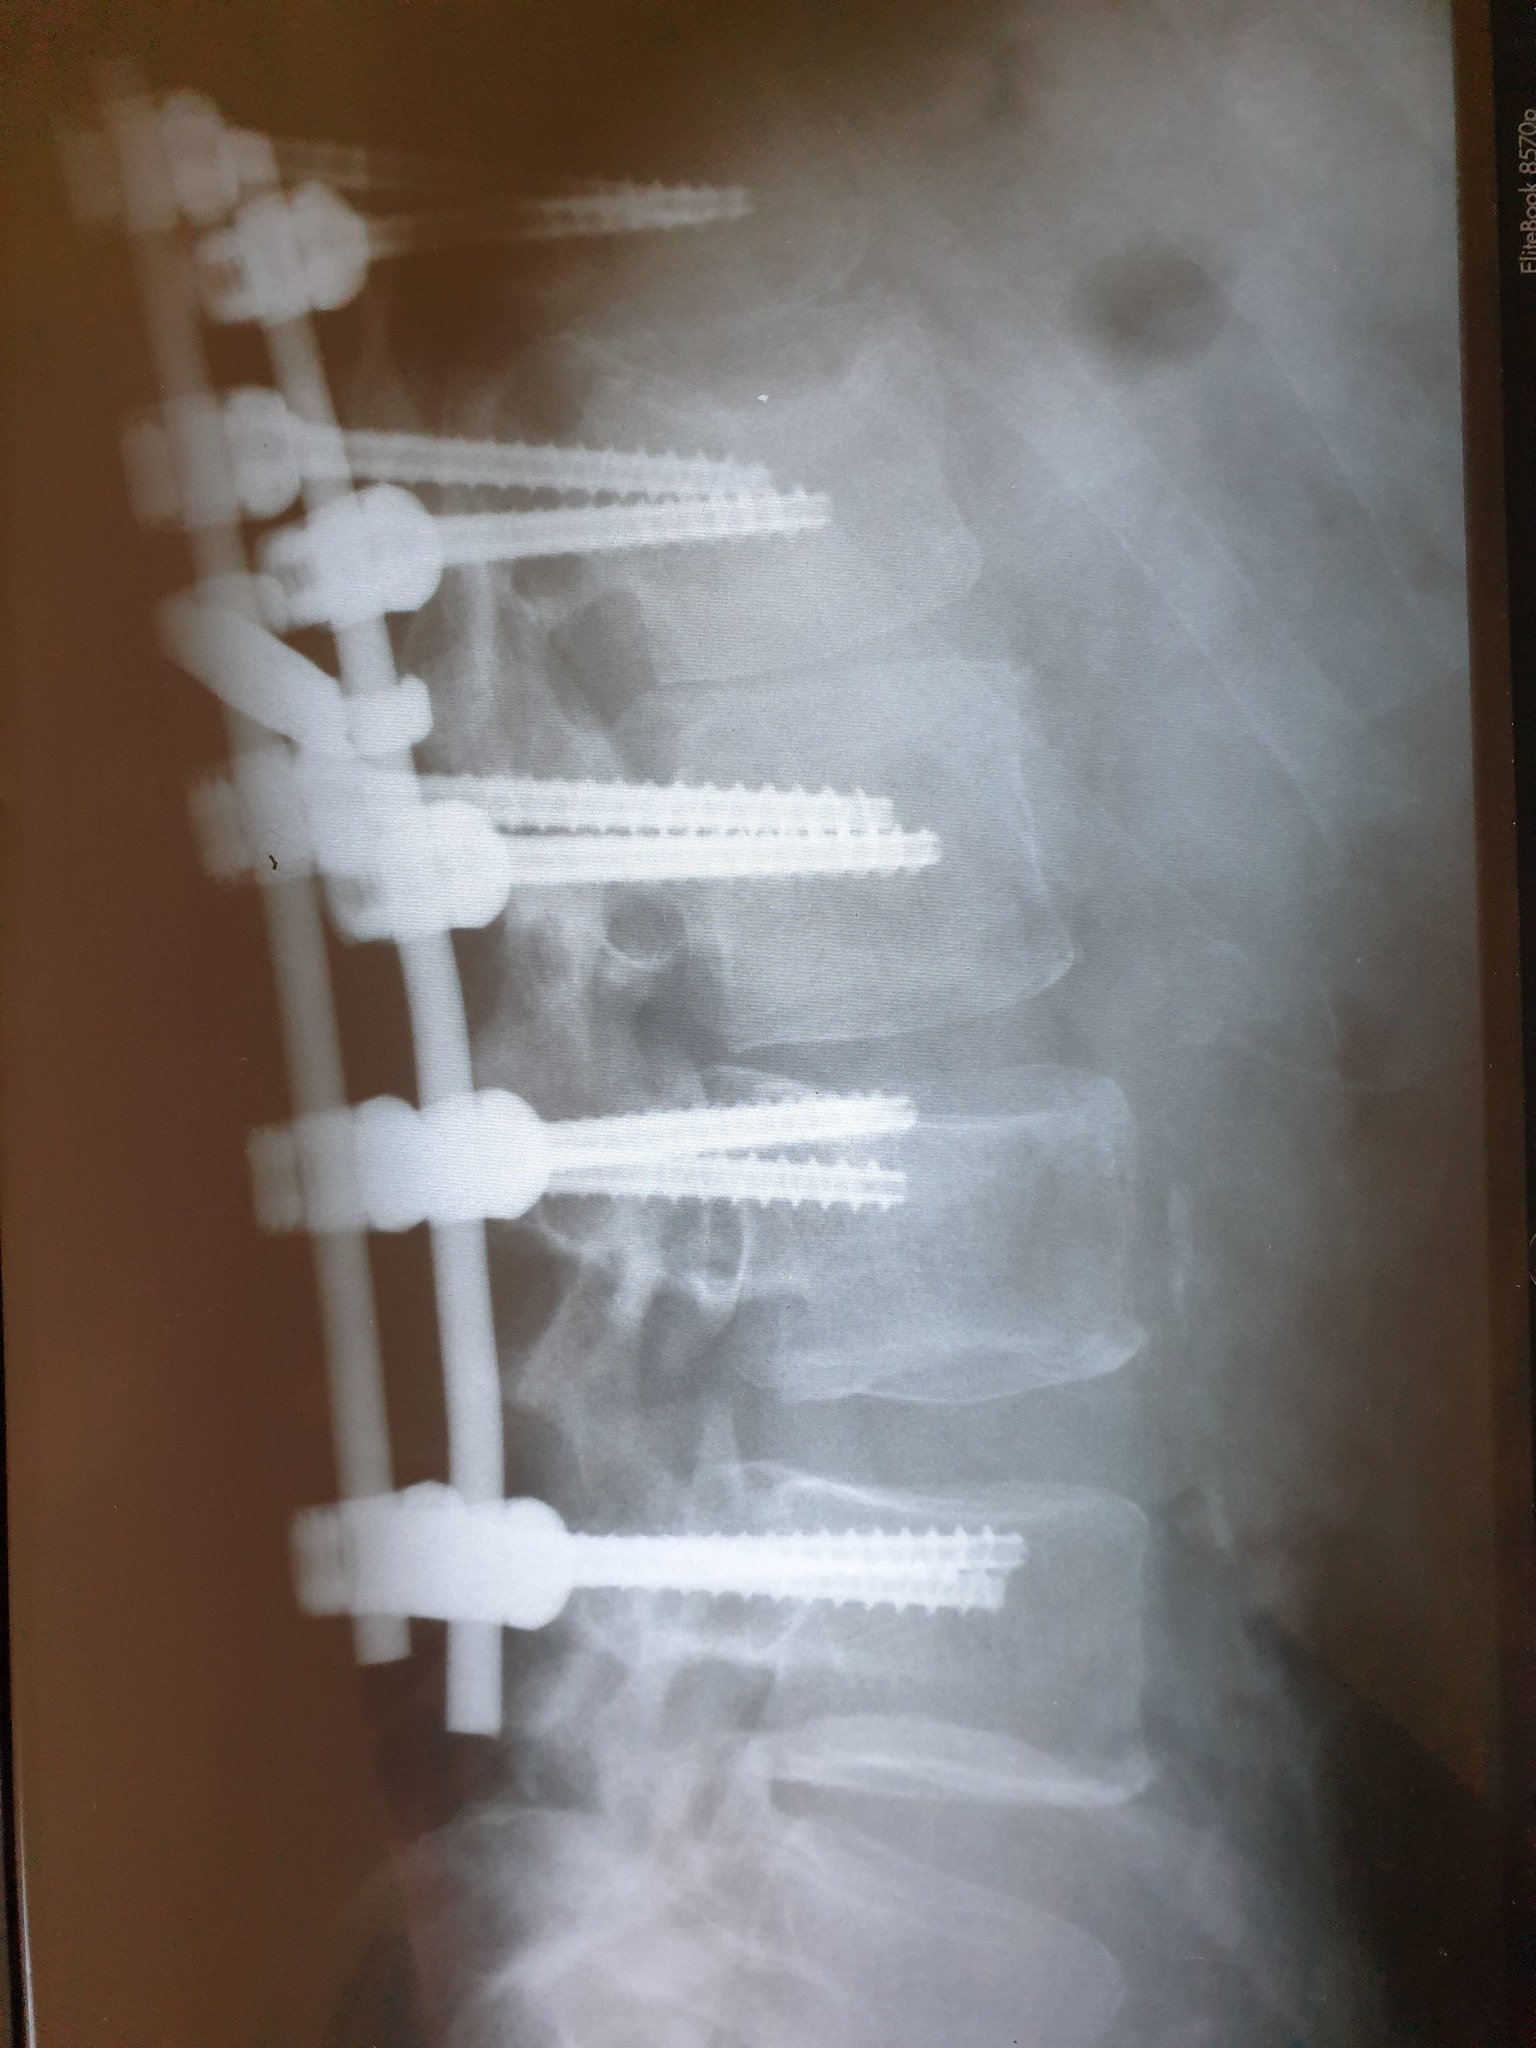

Nakon što je 11. februara doživio povredu na radnom mjestu, tačnije nakon što je pao sa lotri i slomio kičmu na dva mjesta Nino Katić je odlučio da progovori i sa svima podijeli svoje iskustvo, ali i pokaže zastrašujuće povrede koje je zadobio.

– Šta dobiješ u “Centrumu” kada zbog njihovog neispravnog sredstva za rad slomiš kičmu na dva mjesta i ostaneš invalid? Pa kod neljudi dobiješ otkaz, i to poštom – rekao je Katić, a zatim je opisao šta je dovelo do teške nesreće koja se dogodila 11. februara, ali i svemu što je slijedilo nakon tog dana.

– Došao je i 11. februar, taj crni 11. kada sam pao sa lotri, samo pukoše ispod mene i završio sam sa dvostrukim lomom kičme. Inspekciju nisu zvali, jedva je i Hitna pozvana, a kažu prva riječ šefova je bila: “Jeste li morali zvati Hitnu?”, Nakon toga me je zamjenica porodične doktorke oštetila svojim neradom jer mi nije htjela na vrijeme izdati uputnicu za ljekarsku komisiju na koju sam zbog toga zakasnio dva dana i uslijed čega mi je ljekarska komisija promjenila status iz “povreda na radu: DA” u “povreda na radu: NE”, znači svjesno se lagalo na zvaničnom dokumentu – objasnio je Katić za Srpskainfo.